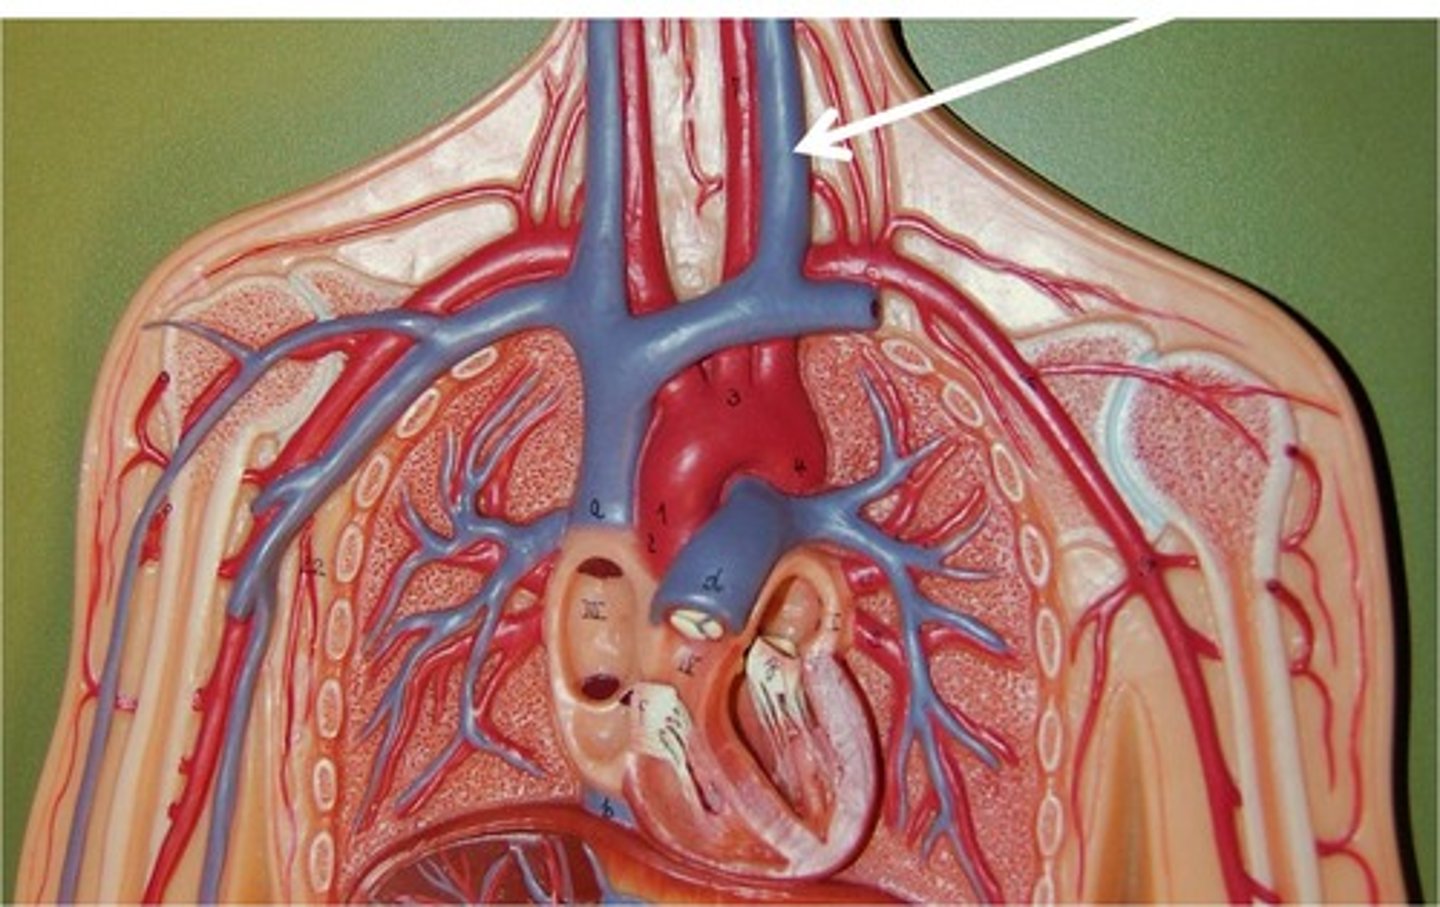

Common carotid arteries:

-Left originates from the _____

-Right arises from the _____

-Ascend the _____ aspect of the neck

-Lie _____ to the internal jugular vein and _____ to the thyroid lobe

-Course deep to the _____ muscles

-Typically, no _____

-Bifurcate into the _____ and _____ carotid arteries

-Left originates from the aortic arch

-Right arises from the innominate (brachiocephalic) artery

-Ascend the anterolateral aspect of the neck

-Lie medial to the internal jugular vein and lateral to the thyroid lobe

-Course deep to the sternocleidomastoid muscles

-Typically, no branches

-Bifurcate into the external and internal carotid arteries

Internal Jugular Veins:

-Receive the major portion of blood from the _____,_____, and superficial parts of the _____

-Course ______ to the carotid artery

-Unite with the _____ vein, forming the _____ vein

-Right and left innominate veins join, forming the _____

-Receive the major portion of blood from the brain, neck, and superficial parts of the face

-Course lateral to the carotid artery

-Unite with the subclavian vein, forming the innominate (brachiocephalic) vein

-Right and left innominate veins join, forming the SVC